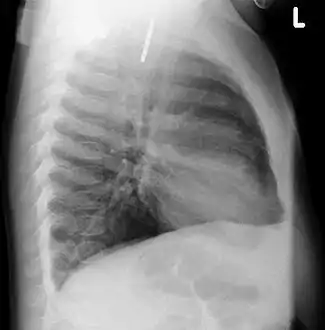

- A coin seen on AP CXR in the esophagus

- A coin seen on lateral CXR in the esophagus